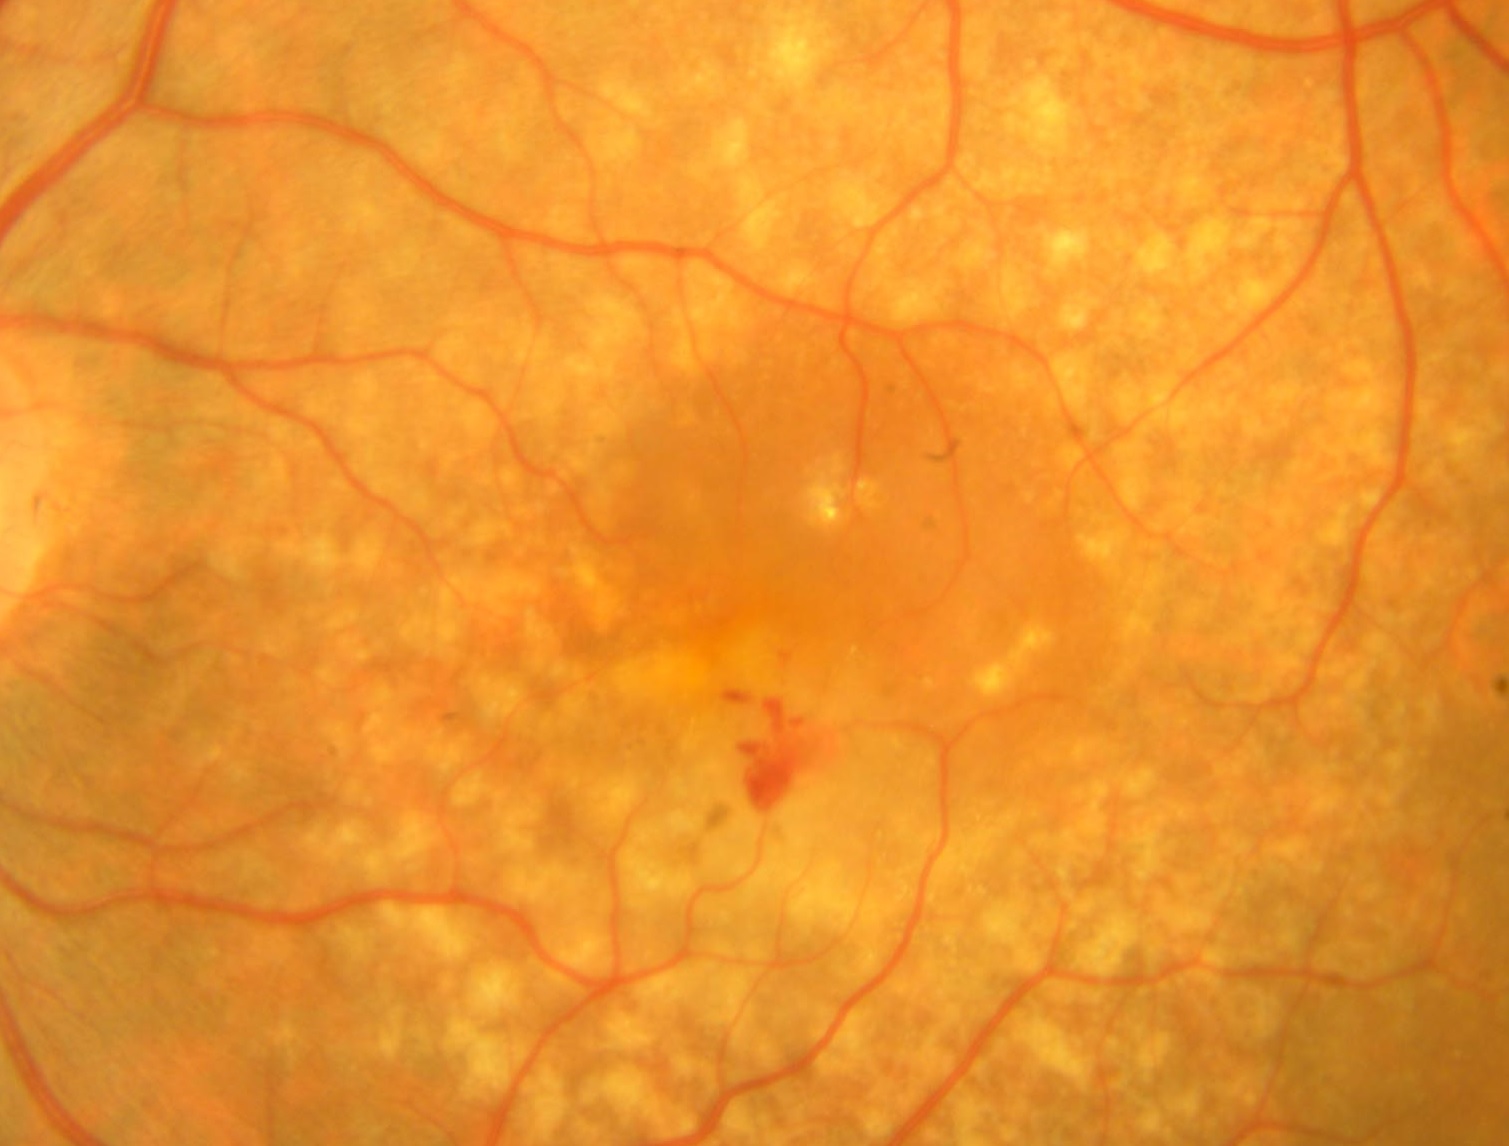

Tag: Degenerazione maculare senile